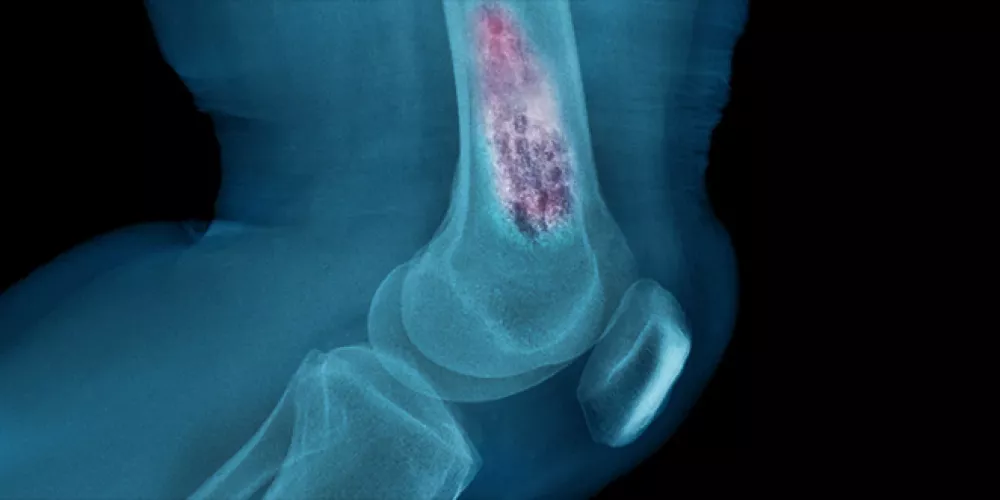

5. السرطان المنتشر

في بعض الحالات، قد لا يكون الورم في الاصل في العظم، بل ينتشر إليه من عضو آخر مثل الثدي أو الرئة أو البروستاتا حيث يعرف هذا باسم “النقائل العظمية”، وغالبًا ما يكون مؤلمًا ويكتشف من خلال الفحوصات الإشعاعية.